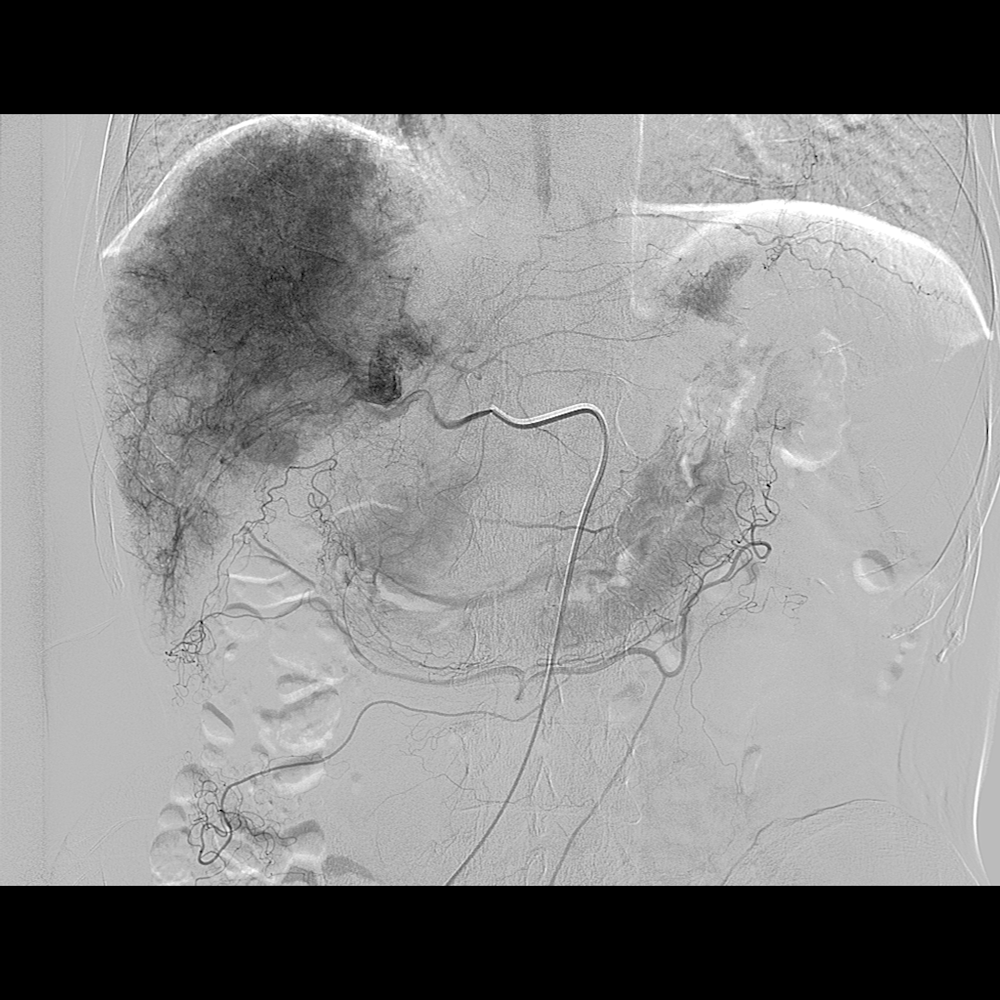

2.外周血管介入手术治疗:腹主动脉血管病症,肝脏肿瘤治疗,肝脏,肺部肿瘤活检,椎体成形术,泌尿系统血管病变等微创介入手术。

DSA造影显示肝癌 通过微导管栓塞病灶,阻断了肿瘤供血,肿瘤逐渐萎缩